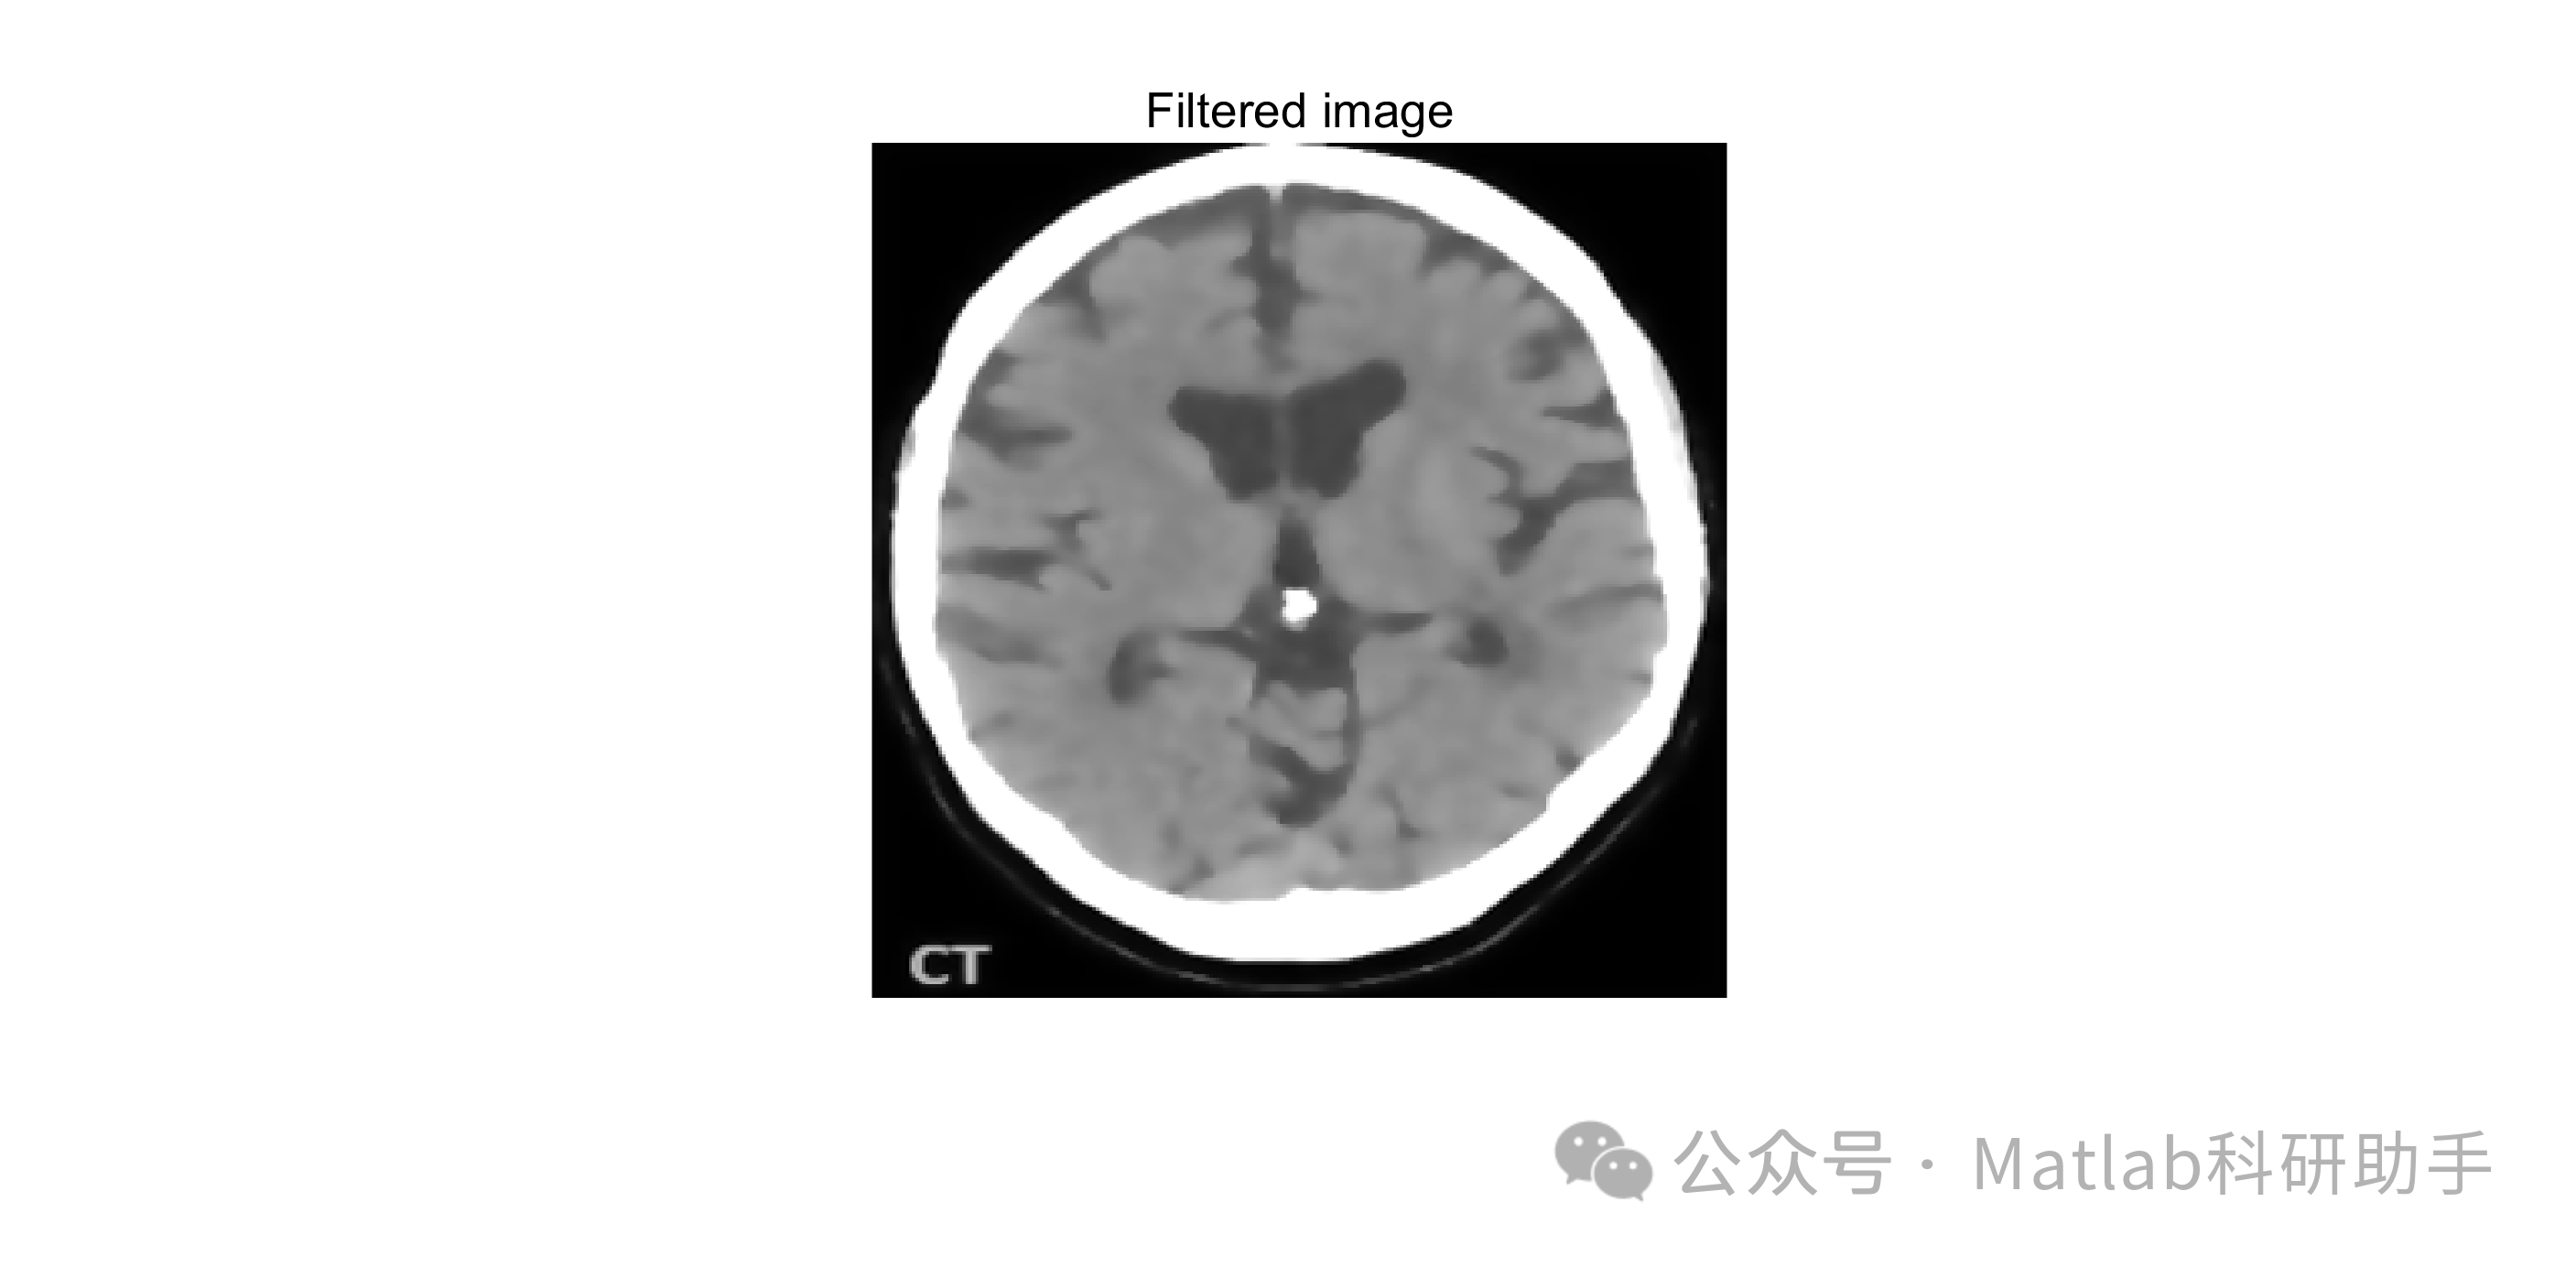

⛳️ 运行结果

各向异性滤波器,作为一种非线性滤波技术,能够克服传统滤波器的局限性。 其核心思想是根据图像局部结构的梯度信息,自适应地调整平滑强度。 在梯度较小的区域,如组织内部,进行较大强度的平滑,有效去除噪声;而在梯度较大的区域,如组织边缘,则进行较小强度的平滑,尽可能地保留边缘细节信息。 这种选择性的平滑方式,不仅能有效抑制噪声,还能增强肿瘤与周围正常组织的对比度,为后续的图像分割奠定良好的基础。

经过各向异性滤波预处理后的MRI图像,其噪声得到有效抑制,肿瘤与周围正常组织的对比度得到增强,为后续的图像分割创造了有利条件。 图像分割是将图像划分为若干个互不重叠的区域,使得每个区域内的像素具有相似的特征,而不同区域之间的像素具有明显的差异。 常用的图像分割方法包括阈值分割、区域生长、聚类分割、水平集分割、深度学习分割等。

利用各向异性滤波器(如Perona-Malik滤波器或Weickert滤波器)对图像进行去噪和平滑处理。 选取合适的参数K和迭代次数,以达到最佳的去噪效果和边缘保留能力。